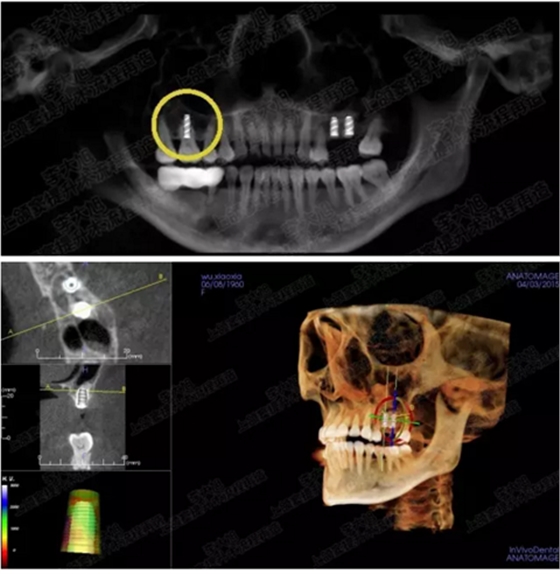

講師簡介

種植牙內(nèi)幕已曝光,低位價的牙你還敢“種”嗎?.png

講師:李大旭

中華口腔醫(yī)學會會員、中華口腔醫(yī)學會種植學會??茣T。畢業(yè)于西安交通大學口腔臨床醫(yī)學醫(yī)學博士。2007-2011年西安交通大學口腔醫(yī)院種植中心、頜面外科醫(yī)師,2011.6-至今為西安交通大學第一附屬醫(yī)院口腔科醫(yī)師。韓國美格真種植系統(tǒng)講師、美國百好瑞種植系統(tǒng)講師、德國kavo影像學院、怡友影像系統(tǒng)講師。